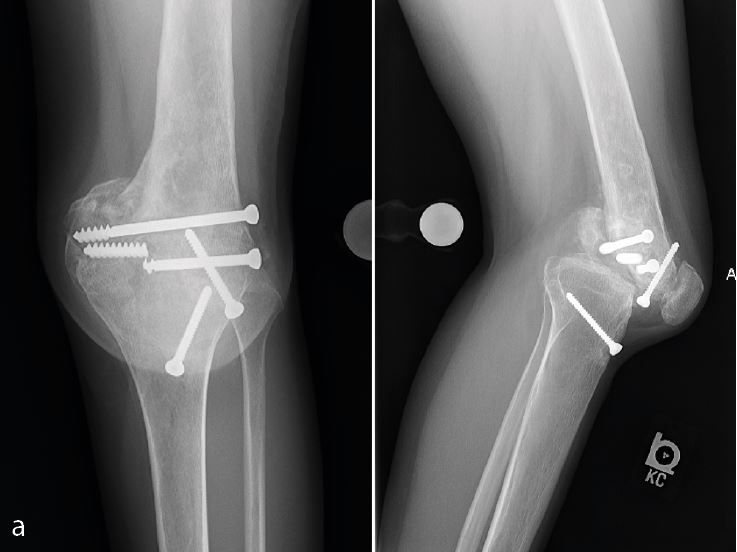

Often the first question is whether or not to remove preexisting hardware at the time of surgery or two-stage prior to knee replacement. Although there have been reports of positive cultures when evaluating removed hardware, I don’t think that prior hardware always needs to be removed before attempting a total knee replacement. Medial hardware on the proximal tibia or distal femur can usually be removed without difficulty through a standard medial parapatellar approach at the time of total knee replacement (Figure 6a, b).

I usually take a careful history of prior infections, open fracture and delayed wound healing after the initial open reduction and internal fixation. I have a low threshold to aspirate knees prior to implantation to exclude the remote possibility of a chronic infection or change my plan to a two-stage procedure if the removed hardware looks suspicious. An MRI imaging might help to detect evidence of osteomyelitis. In the presence of lateral hardware, I usually prefer to remove the hardware in a two-stage fashion. I don’t feel comfortable having a second incision around the knee at the time of a total knee replacement (Figure 7a, b).